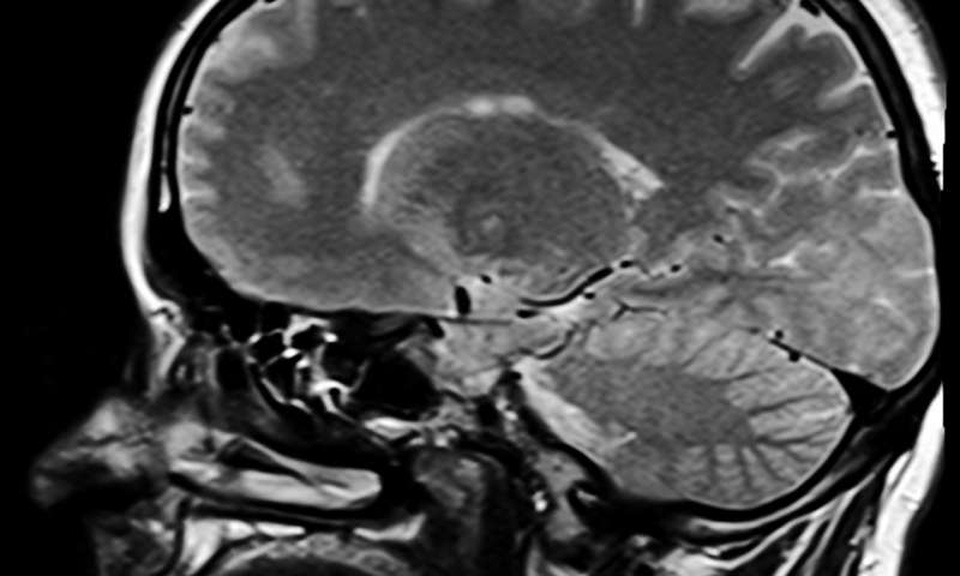

(Dân trí) - Lần đầu tiên các nhà khoa học tại Đại học Manchester đã chỉ ra rằng, nếu não được “điều chỉnh trong” đến một tần số cụ thể thì cơn đau mãn tính có thể được giảm nhẹ.

Lần đầu tiên các nhà khoa học tại Đại học Manchester đã chỉ ra rằng, nếu não được “điều chỉnh trong” đến một tần số cụ thể thì cơn đau mãn tính có thể được giảm nhẹ.

Tế bào thần kinh trên bề mặt của não phối hợp với nhau ở một tần số cụ thể tùy thuộc vào tình trạng của não. Các sóng Alpha được điều chỉnh ở 9-12 chu kỳ trong mỗi giây mới đây đã được kết hợp với các bộ phận được phép của não liên quan đến khả năng kiểm soát cao hơn để ảnh hưởng đến các bộ phận khác của não.

Các nhà nghiên cứu tại Tập đoàn Nghiên cứu về Đau ở người(Human Pain Research Group) tại Đại học Manchester cho thấy sóng alpha từ phía trước của não, não trước, được kết hợp với thuốc giảm đau giả dược và có thể ảnh hưởng đến cách mà các phần khác của não gây đau.

Điều này dẫn đến ý tưởng rằng nếu chúng ta có thể “điều chỉnh” bộ não để thể hiện nhiều sóng alpha hơn, có lẽ chúng ta sẽ có thể làm giảm đau ở một số người bị các bệnh nhất định.